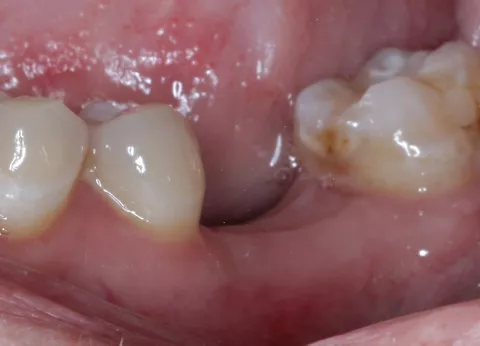

Der 40-jährige, gesunde Patient wurde uns durch seinen Hauszahnarzt mit einer seit mehreren Jahren bestehenden Lücke regio 36 vorgestellt (Abb. 1, 2). Die Nachbarzähne zeigten sich gesund bzw. mit stabilen zahnärztlichen Restaurationen. Trotz der langen Wartephase nach Zahnverlust durch einen progredienten, endodontischen Prozess, war die Schaltlücke ohne Kippung der Nachbarzähne frei und mit der Gegenbezahnung stabil abgestützt. Die Sondierungstiefen der Bezahnung lag in Ober- wie Unterkiefer bei 2 mm (2-Punkt-Messung). Das Weichgewebe in der Lücke zeigte einen ca. 6 mm breiten Saum der attached Gingiva.

Abb. 1: Unterkiefer von okklusal - Schaltlücke regio 36

Abb. 2: Unterkiefer von vestibulär - Schaltlücke regio 36